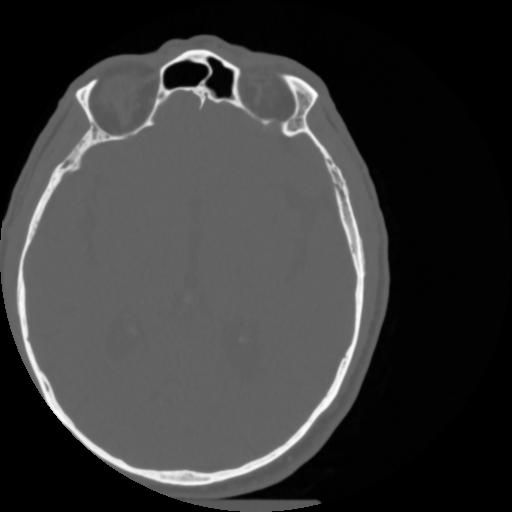

4 CEREBRO,,Vol,0.5,CEREBRO,,